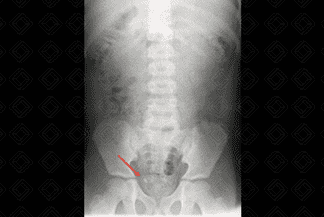

Texto alternativo para a imagem Figura 1. Créditos: Dra. Elazir Mota - Rio de Janeiro/RJ

Descrição da figura 1: Radiografia de abdome normal em decúbito dorsal evidencia a distribuição normal dos gases intestinais. (1) Projeção do músculo psoas bilateralmente; (2) gordura pré-peritoneal normal; (3) hemicúpulas diafragmáticas; (4) cristas ilíacas; (5) reto.

Critérios de bom padrão do exame:

• Visualizar de cúpula diafragmática até sínfise púbica;

• Visualização do psoas;

• Asas ilíacas simétricas;

• Ausência de movimento voluntário.

Rotina de avaliação:

• Visceromegalias;

• Presença de concreções radiopacas (como cálculos, por exemplo);

• Apagamento da linha de gordura pré-peritoneal;

• Avaliação do músculo psoas;

• Distribuição normal do gás nas alças intestinais (procurar dilatação de alças intestinais ou sinais de obstrução);

• Pneumoperitônio (gás fora de alça);

• Fecalomas e massas abdominais desviando estruturas.